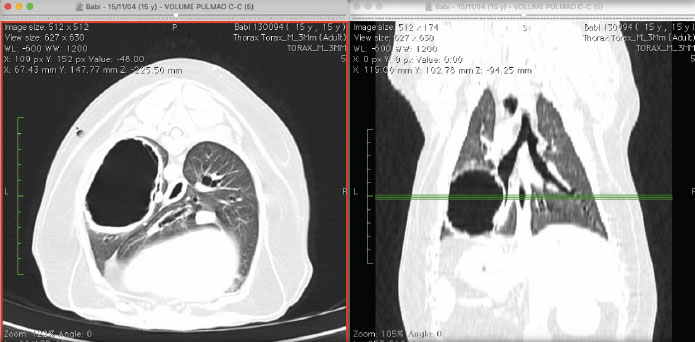

Even though the cardiac silhouette looked normal in the radiography, the dog was diagnosed with moderate mitral insufficiency by echocardiography. The patient was referred to a tomographic examination of the thoracic cavity. The CT images were acquired with a 1-row detector helical CT unit (Somatom Spirit, Siemens; 1,5 pitch, 1s rotation time, 130 de Kv and 70 de mAs). We observed thickening of the bronchial walls and an extensive structure, filled with air, oval to round in shape, with hyperattenuated, thick and irregular walls, approximately 0.4 cm thick (Fig. 2). The CT after intravenous contrast has not been performed, because the owner did not allow it, so the solid part of the tumor could not be contrasted. The structure was located in the perihilar region of the left caudal lung lobe, and it was in contact with its bronchial branches and air bronchogram. It measured approximately 6.6 × 4.5 × 5.9 cm; compatible with aberrant bronchiectasis or a low-grade pneumatocele (Fig. 2). This structure created a medial displacement and luminal compression of the main bronchus of the left caudal pulmonary lobe. In the bifurcation of this main bronchus, its branches moved medially and followed the medioventral and mediodorsal walls of the bullae, respectively, with the ventral branch slipping into the lumen of the bullae. We did not observe lymphomegalies.

Fig. 2. Tomographic images in axial (left) and dorsal (right) views, in which we observe the thickening of the bronchial walls. Moreover, we can observe a structure filled with air, of round shape, with hyperattenuated, thick and irregular walls. It is located in the perihilar region of the left caudal pulmonary lobe in contact with bronchial branches and air bronchograms.